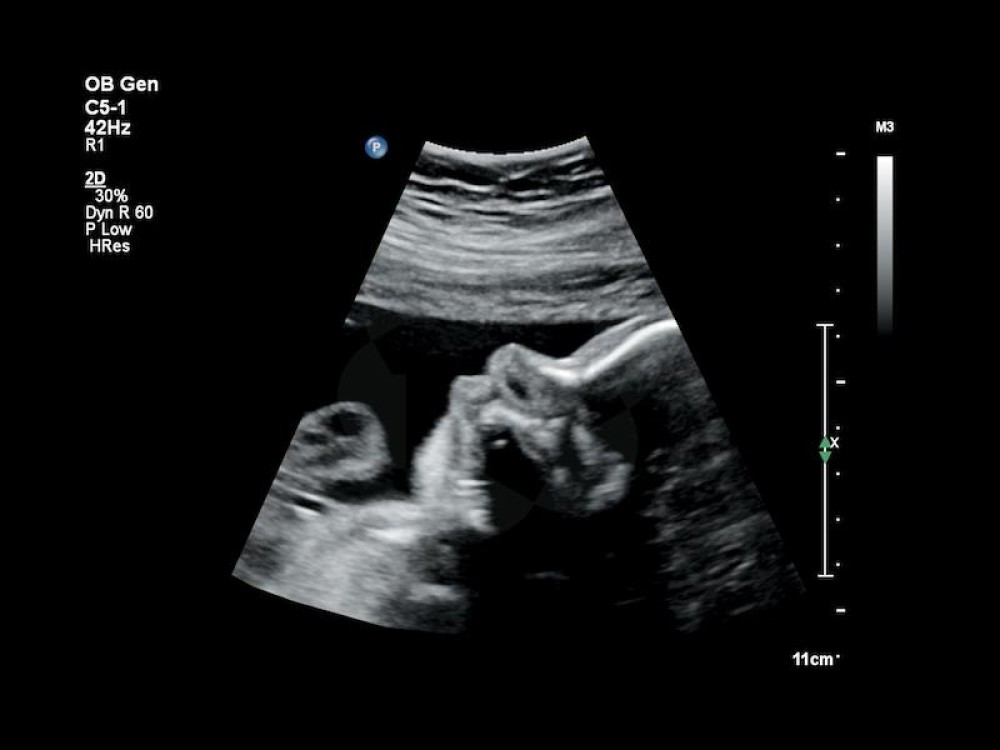

Çox yönlü istifadə: Ümumi görüntüləmə, OB/GYN, vaskulyar və kardiyak müayinələr üçün uyğundur.

C5-1: 1–5 MHz, qarın və obstetrik görüntüləmə.

Obstetrika / Ginekologiya: fetal və reproduktiv orqanların qiymətləndirilməsi.